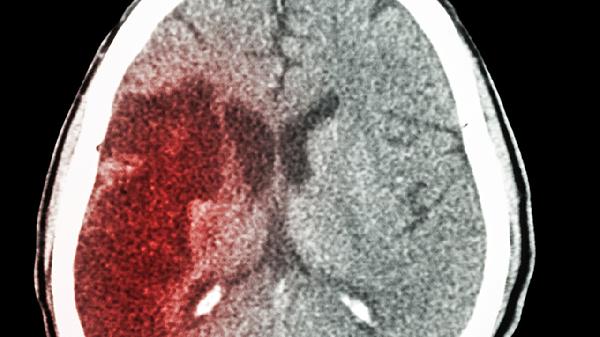

微创手术通过小骨窗或穿刺技术清除血肿,对脑组织损伤较小,术后并发症概率较低。多数患者术后1-3天可恢复意识,3-7天能进行基础肢体活动。手术过程中采用立体定向或神经导航技术,能精准定位血肿位置,减少周围脑组织损伤。术后配合脱水降颅压药物如甘露醇注射液、利尿药物如呋塞米片等治疗,可有效控制脑水肿。对于基底节区出血量30毫升以下的患者,微创手术成功率较高。

部分特殊情况可能增加手术风险。高龄患者合并高血压、糖尿病等基础疾病时,术后易出现心肺功能异常。凝血功能障碍患者术中再出血风险增加,需提前使用维生素K1注射液等药物调整凝血功能。脑干或丘脑等重要功能区出血,即使采用微创技术也可能遗留吞咽困难、肢体瘫痪等后遗症。术后需密切监测24-48小时生命体征,警惕迟发性颅内血肿形成。